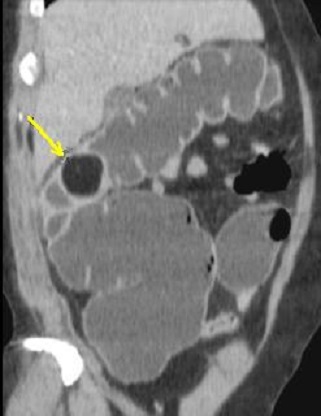

Aspect de même polyp

en vue par technique Coloscopie virtuelle **

. |

Image d'une masse arrondie a

hypodense situe au angle colique droit . Aspect

d'une lipome du colon droit . Image radiologique de

coloscanner a l'eau |

La difference de coloscanner

a l'eau et la TDM de sans preparation est il n'a pas

d'air dans le colon et image de la paroi du colon de

la lesion est plus net ( plus hyperdense ) que la

TDM normale |